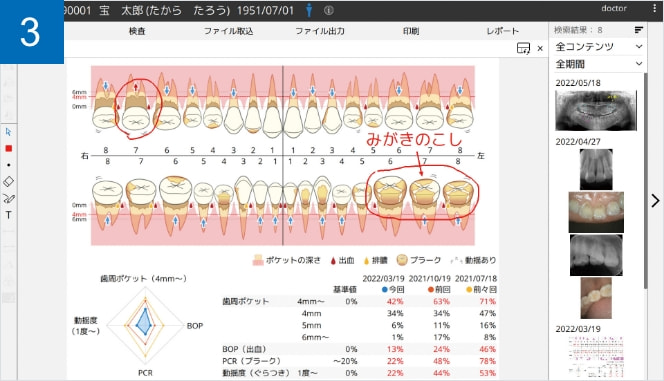

タイムライン表示

過去から現在までの口腔内データを時系列で追跡し、変化の積み重ねを“見える化”することで、診断はもちろん、予防・メンテナンスの説明も支援します

MyGate オプション機能「 X perio(クロスペリオ) 」

歯周病検査の記録やプレゼンテーションを行う事ができる追加可能なオプション機能です。提供文書の印刷までのフローを、スムーズかつ効果的に行えます。

患者説明

検査結果をわかりやすいイラストで表示。

今回・前回・前々回の統計情報とレーダーチャートで経過を確認でき、患者さんのモチベーションの向上・維持に役立ちます。タッチペンで自由に説明を描き込むことができ、説明した内容をそのままMyGateで保存/閲覧することができます。